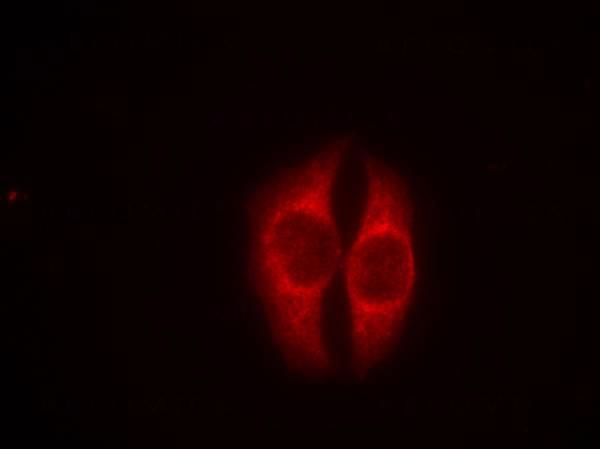

Figure 1: Immunofluorescence staining of methanol-fixed Hela cells using p53(Phospho-Ser37) Antibody 35-1095 .